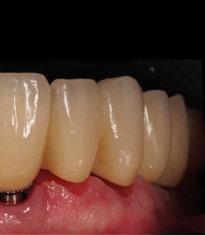

directamente a cabeza de implante para realizar una prótesis dentoalveolar de cerámica de 3 piezas, que equilibraran la oclusión y dieran soporte al labio y la mejilla (Figuras 14-17)

Figura 14. Imagen intraoral frontal postoperatoria al año de la reconstrucción.

Figura 15. Detalle de prótesis dentoalveolar cerámica en visión lateral.